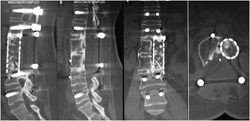

图3-7,后路肿瘤切除照片显示肿瘤切除后T12,L1至L4,L5椎弓根螺钉固定,L1-3椎体间钛网植入,左侧L2神经根切除。

图3-8,术后标本,标本CT平扫与术前图像对比,显示整块肿瘤切除的范围,切除边界充分。

图3-9,术后X片及CT显示肿瘤切除后内固定重建。

术后病理证实:高分化软骨肉瘤。病人术后左侧髂腰肌肌力减弱,其余下肢肌力5级;术后7天下地活动,可走平路。术后3个月复查时左下肢肌力基本正常,病人可正常行走。术后随访33个月,肿瘤无复发,内固定稳定。

图3-10,术后33个月X片,MRI和CT显示,肿瘤无复发,内固定稳固。